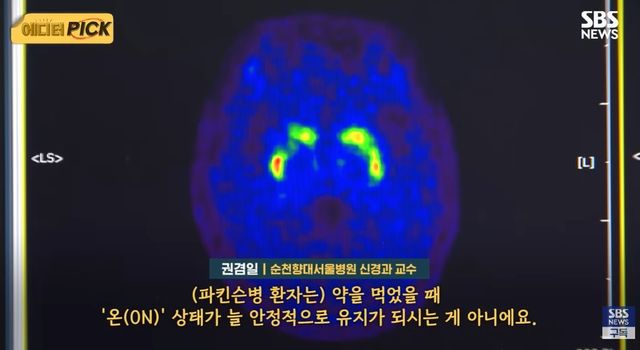

전문가들은 이러한 질환의 특수성이 제대로 반영되지 않고 있다고 지적한다. 권겸일 순천향대서울병원 신경과 교수는 “(파킨슨병 환자는) 약을 먹었을 때 '온(ON)' 상태가 늘 안정적으로 유지가 되시는 게 아니에요. 시력 장애 환자와 동일시해서 장애 평가를 하는 것은, 파킨슨 질환의 특수성을 정말 제대로 반영하지 못하고, 이해하지 못하는 부분이 아닌가….”라고 설명했다.

이 같은 상황은 현행 장애 등급 판정 기준과 밀접한 관련이 있다. 보건복지부는 치료 약물이 있는 질환의 경우, 약을 복용한 상태에서 기능을 평가하는 것이 원칙이라는 입장이다. 시력 장애를 안경 착용 상태에서 판단하는 것과 같은 논리다. 그러나 파킨슨병 환자들에게 약물은 일시적인 효과만을 제공할 뿐이다. 약을 복용하면 잠시 증상이 완화되지만, 약효가 떨어지면 다시 운동 장애가 나타나는 ‘온(ON)·오프(OFF)’ 상태가 반복된다.